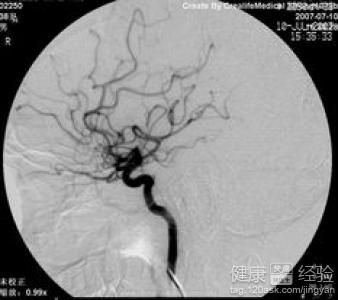

腦血管病發病前的先兆